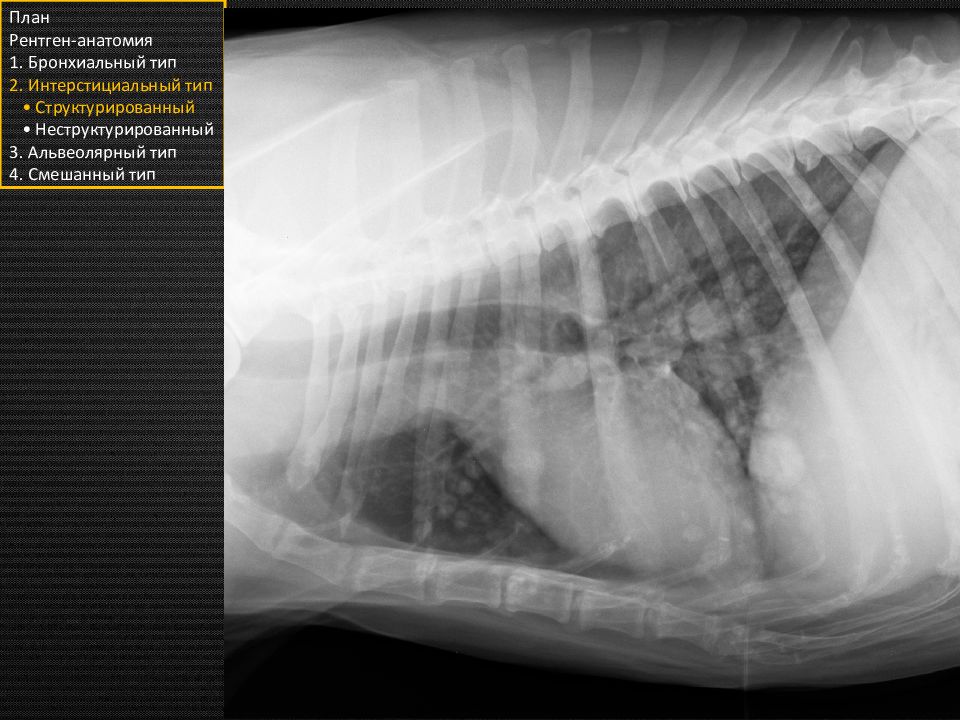

Множественные полностью рентгенопрозрачные очаги более 10 мм в диаметре План Рентген-анатомия 1. Бронхиальный тип 2. Интерстициальный тип • Структурированный • Неструктурированный 3. Альвеолярный тип 4. Смешанный тип